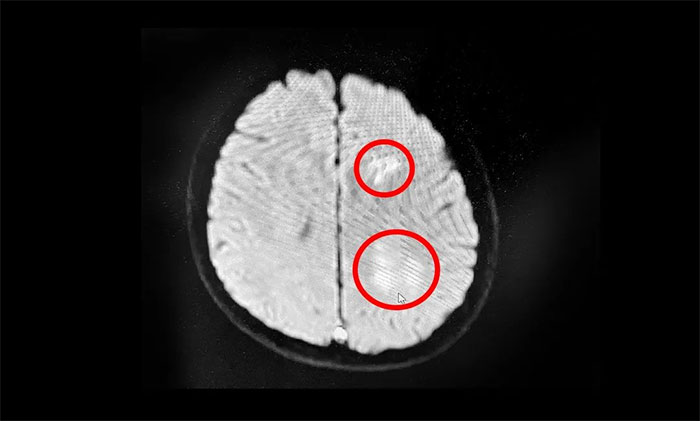

▲MR提示:左側(cè)額頂葉多發(fā)(靜脈性)腦梗塞

據(jù)了解,該患者因突發(fā)頭痛頭暈,輾轉(zhuǎn)多家醫(yī)院,治療未果。醫(yī)院神經(jīng)重癥監(jiān)護8A病區(qū)張慶成主任仔細分析患者病情后,立即為其安排行磁共振檢查。綜合影像和患者癥狀,以及進一步行DSA檢查。最終,該患者確診為腦靜脈竇血栓,合并蛛網(wǎng)膜下腔出血。